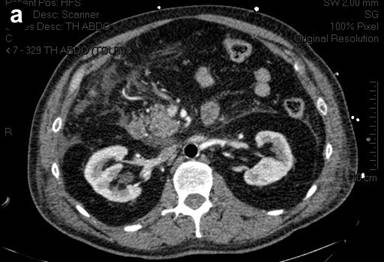

A 58-year-old man with a medical history of dilated cardiomyopathy diagnosed in 2001, with a left ventricular ejection fraction of 35%, was admitted to our ICU in January 2010 following cardiac arrest. In the morning, he had gone hunting, and did not have any symptoms. After returning home, while he was seated and without any prodrome, he presented lost consciousness and fell on the floor. There was no sign of breathing and no cardiac activity. Cardiopulmonary resuscitation was immediately started by his son-in-law, a professional fireman. At minute 20 after cardiac arrest, a professional team of firemen arrived and a semi-automatic cardiac defibrillator delivered 4 electric shocks. At minute 50, an emergency medical team arrived; electrocardiogram revealed asystolia, and intravenous adrenaline (epinephrine) was administered. A return to spontaneous cardiac activity was obtained at minute 80. Cardiopulmonary resuscitation was never interrupted during these 80 minutes, and no mydriasis was noted. An electrocardiogram showed abnormalities of the ST segment with suspicion of posterior myocardial infarct. The patient was transferred to our University Hospital. Coronarography showed no sign of arterial obstruction, and the left ventricular ejection fraction was 50%. An intra-aortic balloon pump was begun. The patient was then admitted to our ICU, with a presumed diagnosis of cardiac arrest secondary to ventricular arrhythmia, complicating dilated cardiomyopathy. The Organ Dysfunction and/or Infection (ODIN) score [4] at admission was 4 and the Simplified Acute Physiology Score (SAPS II) score [5] was 76 on the first day of admission, reflecting the poor prognosis of the patient. Hemodynamic status was initially stable under adrenaline infusion and intra-aortic balloon pump. As there was severe hypoxia with signs of aspiration pneumonia, antibiotic therapy directed against gram-negative and anaerobic bacteria was started. Abdominal volume was increased, with tension, but without diarrhea or digestive bleeding (Figure 1). Biologically, the lipase concentration was 866 IU/L (reference range: 0-60 IU/L). The arterial lactate concentration measured after the prolonged cardiopulmonary resuscitation was 10 mmol/L (reference range: 0.3-2.5 mmol/L); it rapidly decreased to 2.5 mmol/L 24 hours after admission to the ICU. During the ICU stay, the arterial lactate concentration remained normal. The patient was oliguric, with acute renal failure and metabolic acidosis; therefore, continuous veno-venous hemodiafiltration was started. Therapeutic hypothermia using an external cooling device to a target temperature of 33°C was carried out during the first 24 hours. In the following days, the intra-aortic balloon pump and adrenaline were stopped, hypoxia rapidly improved, and renal function normalized. However, abdominal examination did not improve, and there was no sign of awakening despite the cessation of sedation. An abdominal CT scan confirmed the diagnosis of acute pancreatitis with a CT severity index of 4 (Figure 2), and a cerebral CT scan revealed diffuse hypodensity with severe ischemic brain edema. After eight days in the ICU, in the absence of awakening, a therapeutic limitation was decided, leading to death.

Figure 2. Abdominal CT scan showing acute pancreatitis with a CT severity index of four. |